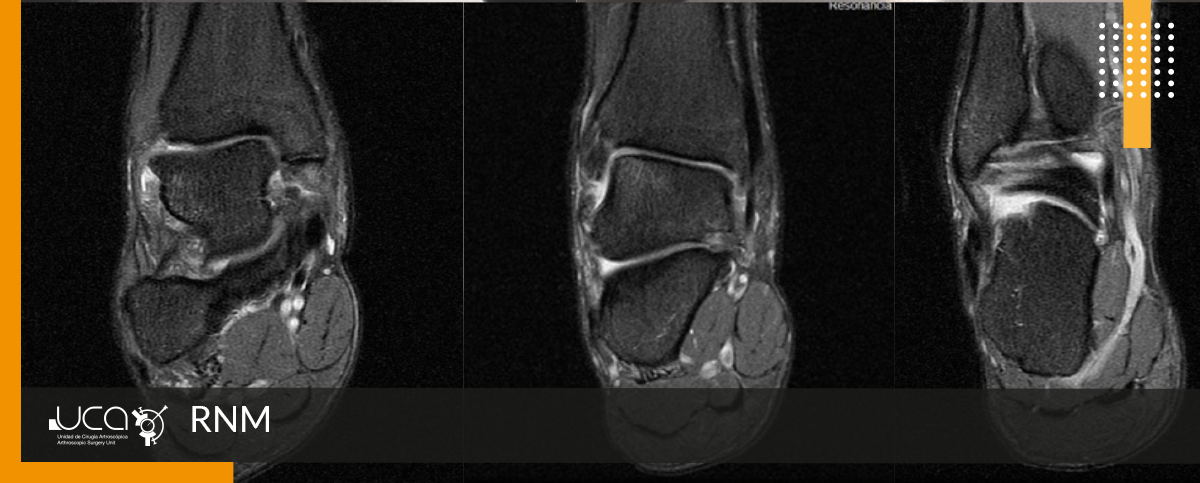

Se encuentra un edema en ángulo superoexterno de astrágalo. Lesión de ligamento PAA. Edema en subastragalina posterior, derrame tibio astragalino. Engrosamiento de ligamento deltoideo.